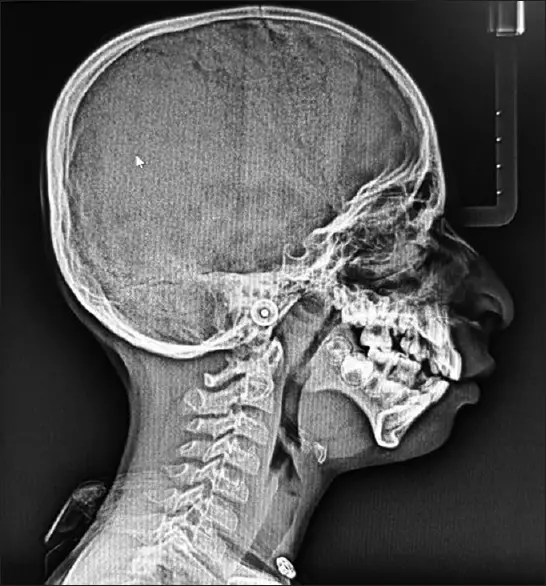

پس از یک سری معاینات، مشاوره و آزمایش ژنتیک، متخصصان پزشکی در نهایت به یک تشخیص قطعی رسیدند؛ سندرم تریچر کالینز (TCS). این اختلال ژنتیکی نادر بر رشد استخوانها و بافتهای صورت در طول رشد جنین تأثیر میگذارد و منجر به ناهنجاریهای صورت و اختلالات شنوایی میشود. اعتقاد بر این است که ناشی از جهش در ژنهای TCOF1، POLR1C یا POLR1D است، اگرچه در برخی موارد، علت ناشناخته باقی میماند.

سندرم تریچر-کالینز که به نام دیسوستوز فک پایین نیز شناخته می شود، یک اختلال ژنتیکی بسیار نادر است که تقریباً از هر 50000 تولد زنده 1 نفر را تحت تأثیر قرار می دهد. اگرچه شدت این بیماری در بین افراد متفاوت است، ویژگی های مشترک عبارتند از: TCS اساساً استخوانها و بافتهای صورت را تحت تأثیر قرار میدهد و در نتیجه استخوانهای گونه، فک و چانه رشد نکرده است. در نتیجه، افراد مبتلا اغلب ظاهری متمایز دارند که با چشمهای متمایل به پایین، گوشهای کوچک و بد شکل و چانه عقبرفته مشخص میشود.

علاوه بر ناهنجاری های صورت، TCS می تواند منجر به از دست دادن شنوایی به دلیل ناهنجاری ساختارهای گوش میانی شود. کم شنوایی در میان افراد مبتلا به TCS رایج است و نیاز به مداخلاتی مانند سمعک یا جراحی های اصلاحی دارد.

ساختارهای فک و صورت توسعه نیافته می تواند راه هوایی را مسدود کند و منجر به مشکلات تنفسی، به ویژه در هنگام خواب شود. علاوه بر این، نوزادان مبتلا به TCS ممکن است در تغذیه با مشکلاتی مواجه شوند که نیاز به مراقبت های تخصصی و تکنیک های تغذیه ای دارد.